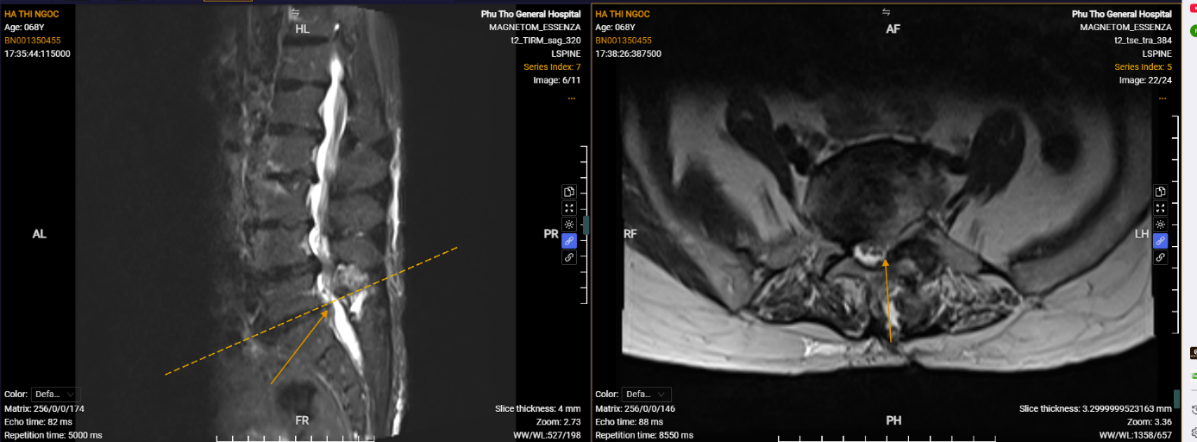

Hình ảnh phim chụp của người bệnh Hà Thị Ngọc sau phẫu thuật.

“Nhờ các bác sĩ khoa Ngoại Thần kinh tư vấn và được PGS.TS Nguyễn Văn Sơn – Phó Giám đốc Bệnh viện trực tiếp phẫu thuật, tôi gần như hồi phục hoàn toàn chỉ sau 10 ngày”. Đó là những lời chia sẻ của người bệnh Hà Thị Ngọc trước khi ra viện và người bệnh cũng không quên gửi lời cảm ơn đến PGS.TS Nguyễn Văn Sơn, BSCKII Hà Xuân Tài – Trưởng khoa Ngoại Thần kinh cùng đội ngũ bác sĩ, điều dưỡng của Bệnh viện đã tận tâm chăm sóc, điều trị cho mình trong thời gian nằm viện.

Người bệnh Hà Thị Ngọc không còn đau đớn, sức khỏe ổn định và tự đi lại sau phẫu thuật.